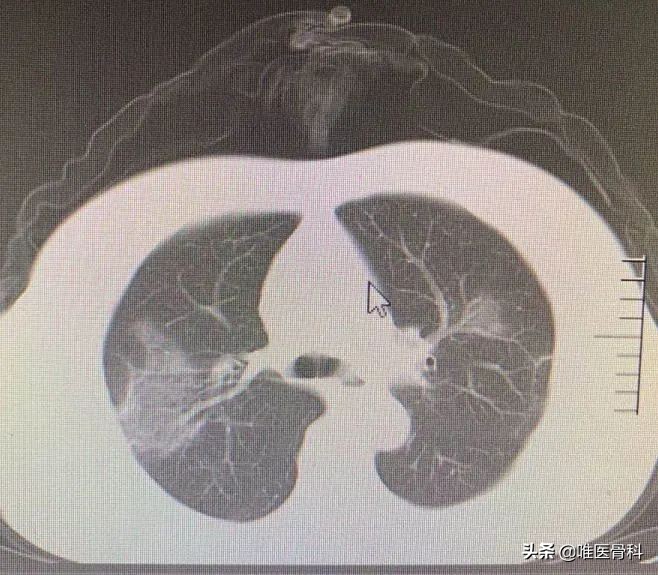

放好药,马不停蹄地赶往汉口医院。到达后我直接去CT登记室取母亲的胸部CT片子,看到片子的时候心里五味杂陈。母亲入住汉口医院后,血氧饱和度一直维持在92%左右,我以为她的情况逐渐趋于稳定,但是CT的片子竟是这么差:几乎各个层面都有渗出病灶,病变范围遍布整个肺野。

19号,母亲复查了胸部CT,虽然炎性病灶没有完全吸收,但是对比汉口医院的那次检查,已经好了很多。

母亲的胸部CT复查结果。CT是在出院前4天做的,虽然渗出病灶没有完全吸收,但是比起在汉口医院时,已经好转